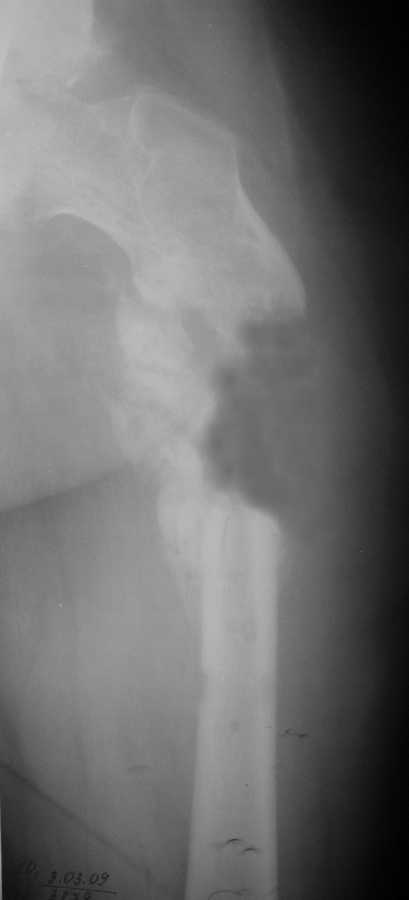

Уважаемые коллеги, у пациента 26 лет имеется дефект в\з бедренной кости образовавшийся в результате СНЭ по поводу травматического остеомиелита

Также имеется травматическая деформация таза с трансвертлужным переломом на стороне дефекта. Планируется замещение дефекта транспортом кости.Хотелось бы услышать ваши советы по поводу оптимальной компоновки АВФ (стержневой, спице-стержневой), есть ли необходимость в дополнительной фиксации за кости таза?

Дефект бедра транспортом тут можно пока не замещать, это долго, муторно, и, главное, не решит проблему создания опорной и безболезненной конечности. Остеосинтез бедра тут одна из подзадач. И решить ее можно относительно быстро - восстановить ось бедра аппаратом (можно как спицевым, так и стержневым) за 10-15 дней, и

сделать закрытый интрамедуллярный остеосинтез. В дефекте есть признаки костеобразования, так что вполне ожидаемо сращение.

Нужды в транспорте кости аппаратом не видно, потому что это не сегментарный, а краевой дефект, и такие дефекты можно закрыть дополнением аутокостью из крыла.

Для уверенности сперва можно ограничиться дебридментом с укладкой временного спейсера, а через некоторое время сделать костную пластику. Фиксацию вместе интрамедуллярного штифта предпочтительно сделать пластиной, которую при дебридменте можно установить с меньшим усилием. Такая пластина локализирует процесс и снимет опасность инфицирования канала.

4. Дефект бедра сегментарный - в ходе операции удалён фрагмент бедренной кости до 7 см.

5. Думаю что с учетом характера возбудителля вероятность выживаемости аутотрасплантата достаточно низкая .